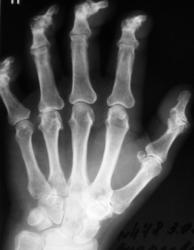

Катенёв Валенти... Дата публикации 25.06.2009, 00:50 Пациент направлен терапевтом в рентгеновский кабинет "на рентгенографию кистей", с диагнозом "Ревматоидный артрит". Ваше мнение коллеги? Чт, 25/06/2009 - 07:54 #1 Андрей Юрьевич Не на сайте Был на сайте: 2 недели 2 дня назад Зарегистрирован: 16.11.2008 - 22:16 Публикации: 18098 Сложно сказать, нет решающего рентген-признака: периартикуллярного остеопороза. В данном случае надежда на лабораторные данные, это ведь и подагрой (см. ниже http://www.radiomed.ru/cases/podaghrichieskii-artrit ) может быть. Андрей Юрьевич Чт, 25/06/2009 - 18:13 #2 OPEXOB Не на сайте Был на сайте: 9 лет 11 месяцев назад Зарегистрирован: 26.07.2008 - 10:02 Публикации: 280 Ревматоидный полиартрит, 4 рентгенологическая стадия. Судя по положению кистей, особенно дистальных фаланг имеет место контрактура данных сочленений. Анализы? СОЭ? Клиника? Чт, 25/06/2009 - 18:45 #3 Андрей Юрьевич Не на сайте Был на сайте: 2 недели 2 дня назад Зарегистрирован: 16.11.2008 - 22:16 Публикации: 18098 ///Анализы? СОЭ? Клиника?/// Выходит Петр. Он ужасен, Движенья быстры, Он прекрасен, Он весь как божия гроза (с) Андрей Юрьевич Чт, 25/06/2009 - 19:20 #4 OPEXOB Не на сайте Был на сайте: 9 лет 11 месяцев назад Зарегистрирован: 26.07.2008 - 10:02 Публикации: 280 Ха,ха, очень смешно!

Сложно сказать, нет решающего рентген-признака: периартикуллярного остеопороза. В данном случае надежда на лабораторные данные, это ведь и подагрой (см. ниже http://www.radiomed.ru/cases/podaghrichieskii-artrit ) может быть.

Ревматоидный полиартрит, 4 рентгенологическая стадия. Судя по положению кистей, особенно дистальных фаланг имеет место контрактура данных сочленений.